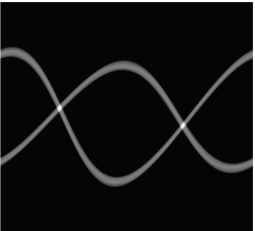

We observe that the weighted projection data admits a sparse representation than the measured projection data in wavelet frame domain. The distributions of wavelet frame coefficients (using piecewise linear tight wavelet frame system) are plotted in Figure 4. To have a fair comparison, and are normalized to the same scale, and the coefficients near the metal trace are removed. From the distributions we can see that the weighted projection data has a sparser representation than the original projection data . Therefore, the sparsity prior in the inpainting model (3.7) is more effective than directly using as input.